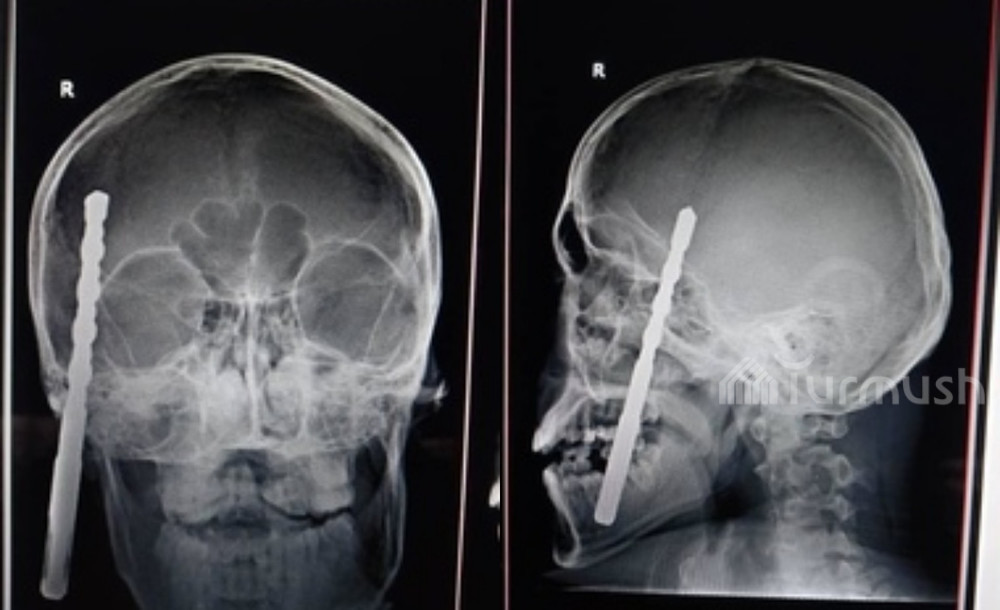

18-летний строитель упал и сверло дрели вонзилось ему в голову — история нейрохирурга А.Идирисова